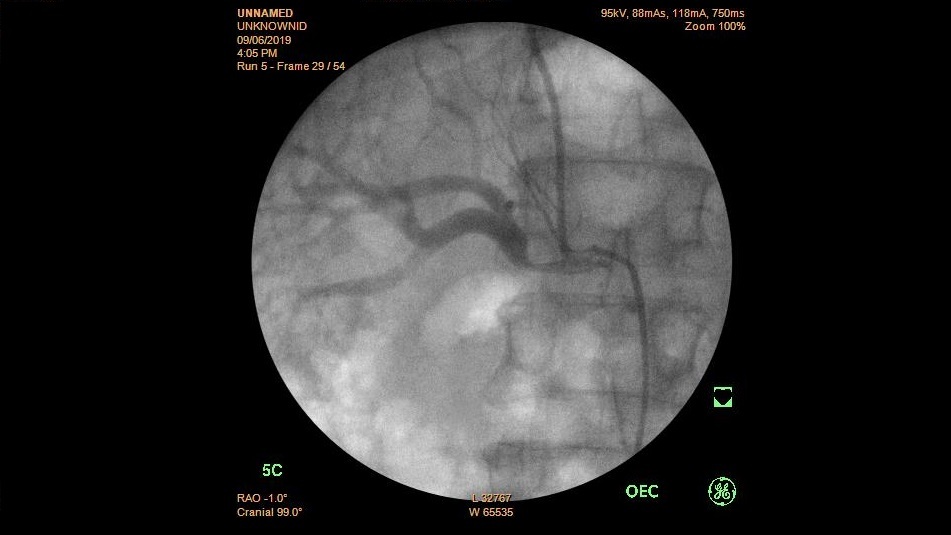

Thông tin Y tế

Nhân một trường hợp đặt stent động mạch thận kích thước lớn

Bệnh nhân Trần Đ., 60 tuổi, tiền sử hút thuốc lá, đái tháo đường, tăng huyết áp điều trị thường xuyên. Tuy được điều trị và theo dõi hàng tháng nhưng...